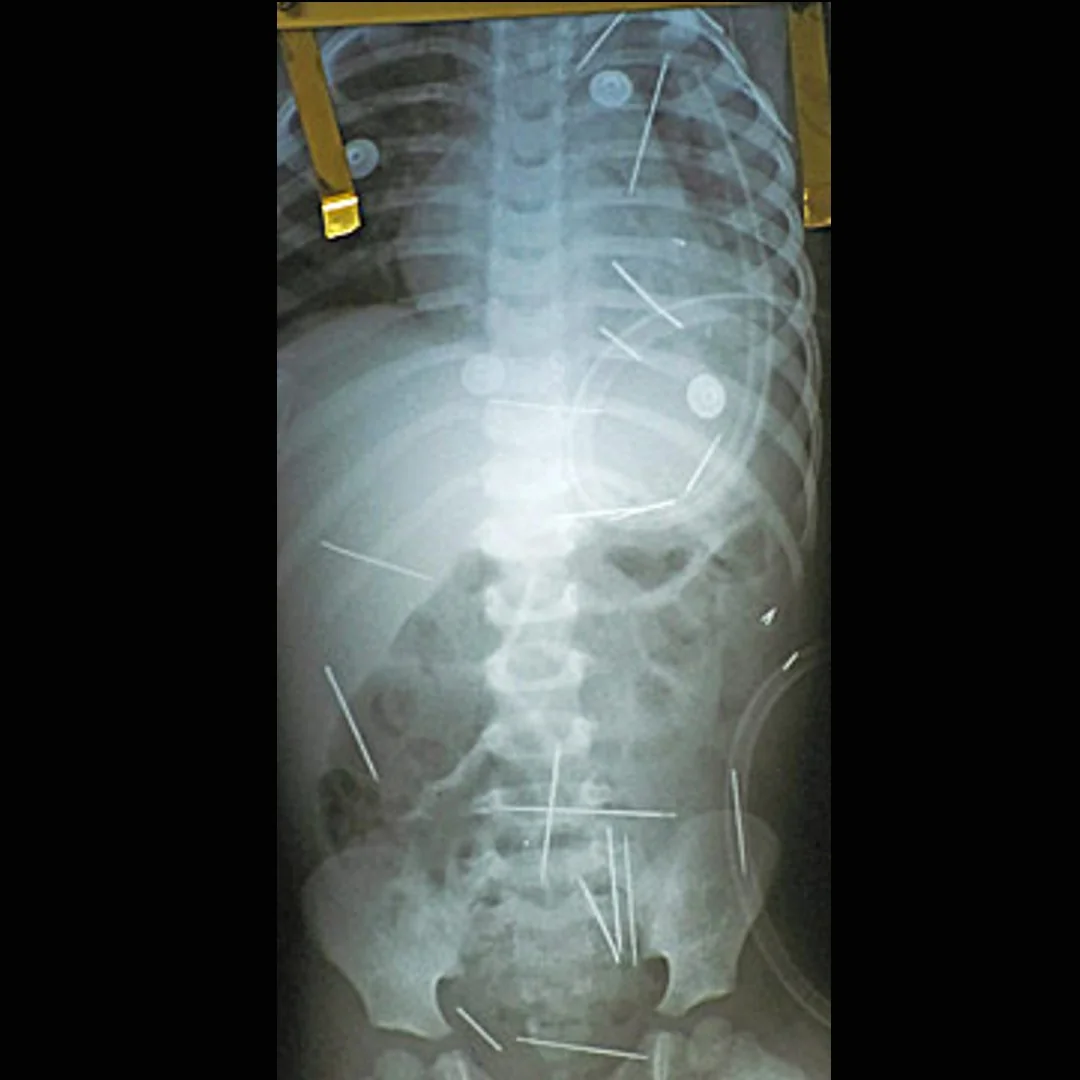

صورة أشعة X -  تظهر الإبر المغروسة

ويقول السيد (ميغالهايس) أن سيدته أخبرته بأن يقتل الطفل من خلال ممارسة طقوس لكي ينتقم من زوجته (أم الطفل). وهكذا بدأ الأطباء بإجراء عملية يوم الخميس في 17 ديسمبر الماضي لإستخراج بعض الإبر من الطفل الصغير بعد أن قامت أمه بنقله إلى المستشفى الذي يقع في الجزء الشمالي الشرقي من ولاية باهيا حيث اشتكت أنه كان عانى أوجاعاً في البطن وإقياء. وأظهرت صور الأشعة السينية X-Ray إبراً تستخدم في الحياكة داخل رقبته وجذعه وسيقانه وكانت إحدى الإبر على الأقل مغروسة في الرئتين والأخرى في الكبد (إنظر الصورة المبينة).